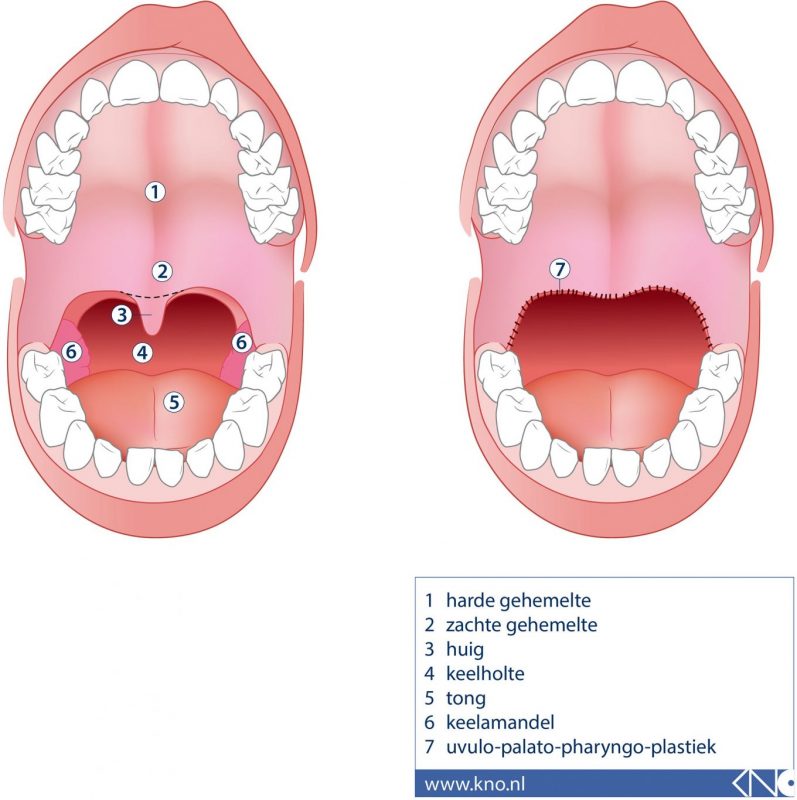

Het dak van de mond bestaat uit het gehemelte dat wordt onderverdeeld in twee delen het harde gehemelte te vinden achter de tanden en het zachte gehemelte te vinden aan de achterkant. Oorzaken van een ontstoken gehemelteverhemelte. De meeste aften genezen vanzelf binnen één tot twee weken. Daar werden twee mogelijke kogelgaten aangetroffen in een raam op de eerste verdieping maar er werden geen kogelhulzen gevonden en er is ook geen sprake van verdere schade. 14022020 - Erkunde Claudia Schneiders Pinnwand Boden Treppe auf Pinterest. Sommige mensen worden daardoor misselijk van het kunstgebit.